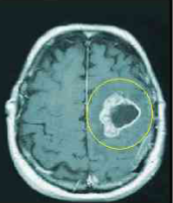

contrast enhancement on outside w/ necrosis on inside

how does a high grade glioma appear on MRI?

low grade glioma

high grade glioma